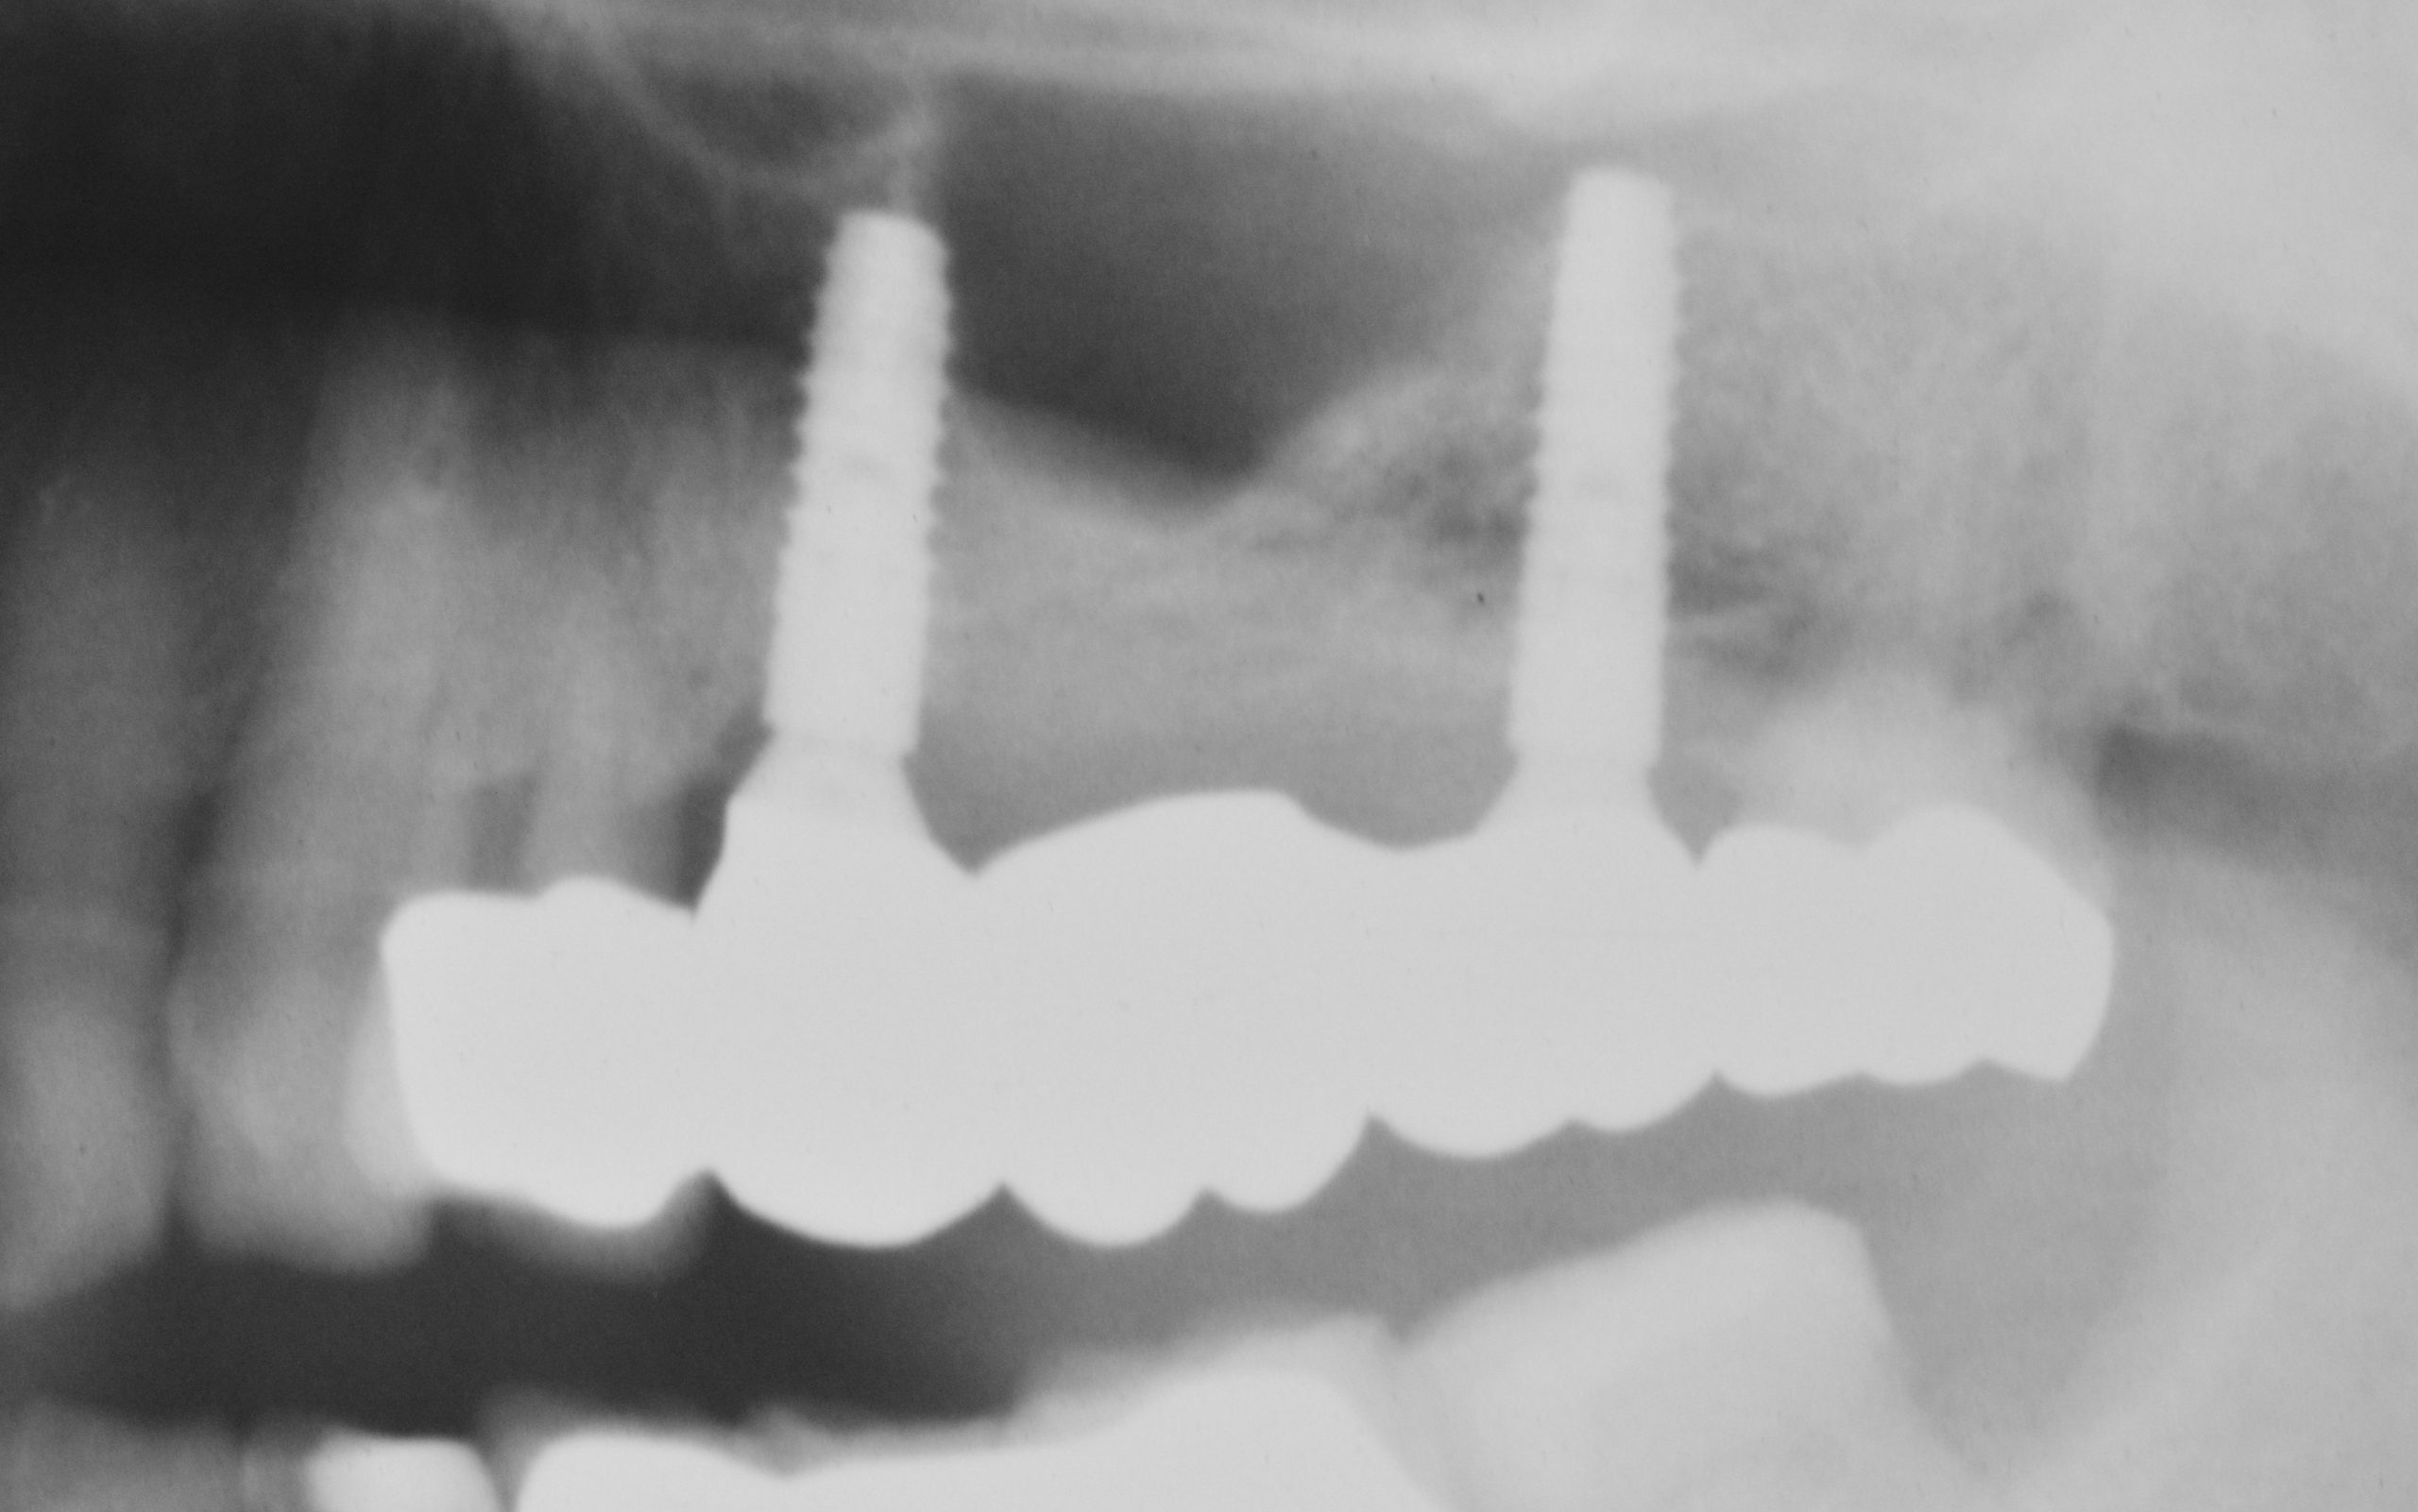

Postoperative control radiograph: the gingiva former at 24 still needs to be retightened.

X-ray control image 23 months after implantation.